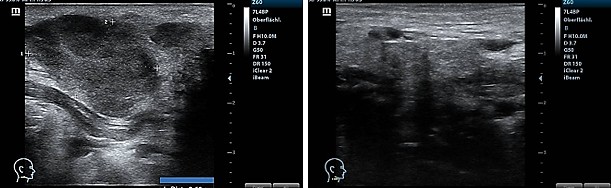

Fig. 3

Fig. 3: Sonography of the parotid-adjacent tumor before TMI treatment (left) and regression two months later after TMI treatment (right).

After five years of being free of symptoms, a rapidly growing, parotid-adjacent tumor on the right side occurred leading to facial palsy. An attempt to surgically remove the tumor was aborted due to risk to the facial nerve. An F-18-FDG PET whole-body CT scan revealed several disseminated hepatic metastases, osseous metastases in the pelvis and in the 5th dorsolateral rib. Histology of a biopsy from a hepatic metastasis as well as from a biopsy of the osteolytic region at the 5th rib, confirmed a recurrence of malignant melanoma. At this moment, the patient was in significantly reduced general condition with bad prognosis. The patient has been receiving oncological combination therapy with two immune checkpoint inhibitors, Ipilumab and Nivolumab. In parallel, an ultrasound-guided, once-weekly piezoelectric TMI treatment in the right parotid region was initiated. For this purpose, the PiezoWave2 device was used with a gel pad (shallow penetration depth Gelpad Nos. 5 and 10). The frequency used was between 2 and 4 Hz per treatment, with 3 Hz being the most common frequency. Depending on pain sensitivity and tolerance, 1000-1500 impulses were applied per session with an energy flux density of 0.12 mJ/mm². Following four immune checkpoint combination therapy sessions and eleven treatments with piezoelectric TMI treatment, a distinct regression after two months and a complete remission of the parotid-adjacent tumor as well as complete concomitant remission of the facial palsy occurred within four months (Fig. 3). Alongside the TMI treatment of the parotid region, TMI treatment of the pelvis metastasis using the PiezoWave2 device was performed simultaneously, precisely localizing the metastatic area measured in the PET-CT scan and based on patient-specific FEM simulation analyses. The deepest penetration depth was achieved with Gelpad 60, at a frequency of 2 Hz. Each treatment delivered 3000 impulses with an energy flux density of 0.35 mJ/mm². In a CT scan six months later, a significant reduction in bone metastases was observed as well as a complete remission of the hepatic metastases not directly treated with shock waves; however, a new pelvic metastasis had occurred. The metastasis at the 5th rib had disappeared (Fig. 4). Though the patient was affected by both the oncological disease and the side effects of the drug therapy, to consolidate and continue the evident therapeutic efficacy, regular TMI treatment of the new metastasis in the pelvic region was resumed with the OrthoGold100® device. The patient was treated 14 times over a six-month period. Each treatment involved a combination of the focused technique with the dark blue applicator and the non-focused technique with the yellow applicator. The deepest penetration depth was selected, along with energy flux density of 0.18 mJ/mm² or 0.27 mJ/mm², applying 2000 impulses per applicator, thus a total of 4000 impulses per session. After TMI treatment, native CT scans showed a distinct regression of the new pelvic metastasis and unchanged sclerosis of the known bone metastases.